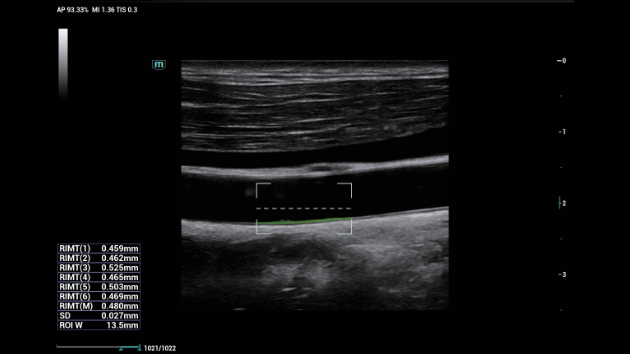

De Consona biedt nieuwe en concrete oplossingen die effici?nt helpen bij het stellen van een vlotte diagnose voor veel verschillende soorten pati?nten.

Ongeacht of u werkzaam bent in een ziekenhuis of kliniek, of uw vaardigheden aanscherpt op het gebied van algemene beeldvormingstoepassingen, vrouwengeneeskunde of cardiovasculaire specialismen, in deze serie vindt u zeer krachtige hulpmiddelen waarmee u aan kop kunt blijven.

Uitgebreide?oplossingen voor beeldvorming aangestuurd door ZST?+

Het ZST+?platform is een buitengewone innovatie en revolutie in de wereld van echografie. Het transformeert echografiegegevens van conventionele bundelvorming naar kanaalgegevensverwerking. Het overwint de traditionele afweging tussen ruimtelijke resolutie, temporele resolutie en weefseluniformiteit, en levert een uitzonderlijke beeldkwaliteit voor oneindige beeldvormingsoplossingen met non-stop verbeteringen.